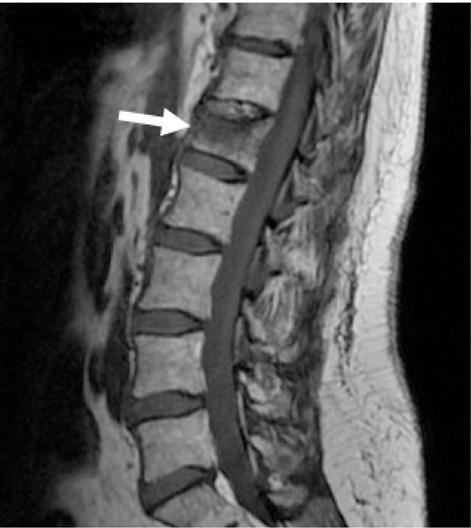

This study includes 22 vertebroplasty procedures performed from October 2018 to July 2020 in 21 patients with traumatic or osteoporotic vertebral fractures (19 female, two men; age between 53 and 89 years). All treatments were executed under fluoroscopic guidance using 11 or 13 G needle through transpedicular or costovertebral unilateral approach. Each patient underwent conscious sedation, continuously monitored by an anesthesiologist. Preoperative MRI images, obtained by 3T or 1.5T MRI scanner, always showed bone marrow edema. The VAS scale and Roland Morris disability questionnaire (RMdq) were administered to patients before and after the treatment to evaluate pain and life quality.

本研究纳入了 2018 年 10 月至 2020 年 7 月期间 21 例创伤性或骨质疏松性椎体骨折患者(19 名女性,2 名男性;年龄 53-89 岁)的 22 例椎体成形术。所有治疗均在透视引导下通过经皮或肋椎关节单侧入路,使用 11 或 13G 针进行。每位患者均在麻醉师的连续监测下接受清醒镇静。术前 MRI 图像由 3T 或 1.5T MRI 扫描仪获得,均显示骨髓水肿。在治疗前后,使用视觉模拟评分(VAS)量表和 Roland Morris 残疾问卷(RMdq)对患者进行疼痛和生活质量评估。